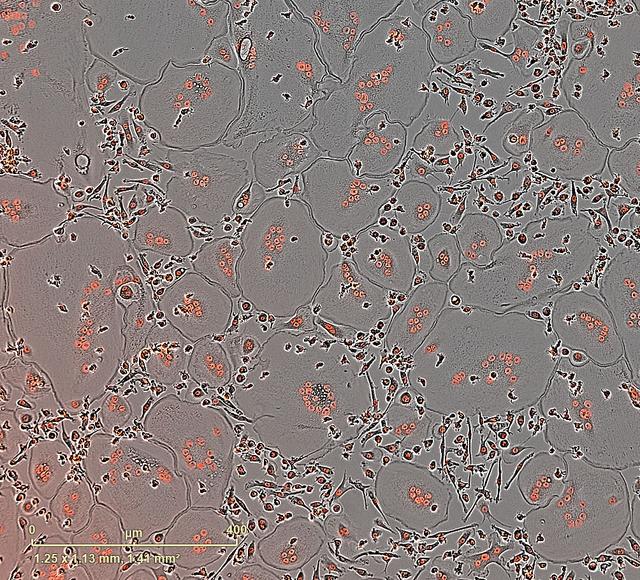

jsc2025e065389 (6/26/2025) --- Bone-forming or mesenchymal stem cells from human bone marrow stained with red dye. An investigation on the International Space Station, Microgravity Associated Bone Loss-B (MABL-B), assesses how these cells respond to microgravity, including changes in gene expression and the secretion of signaling proteins that promote bone formation and increase bone loss. Results could provide insight into bone loss that occurs during spaceflight and from normal aging and disease on Earth. Credit: Mayo Clinic